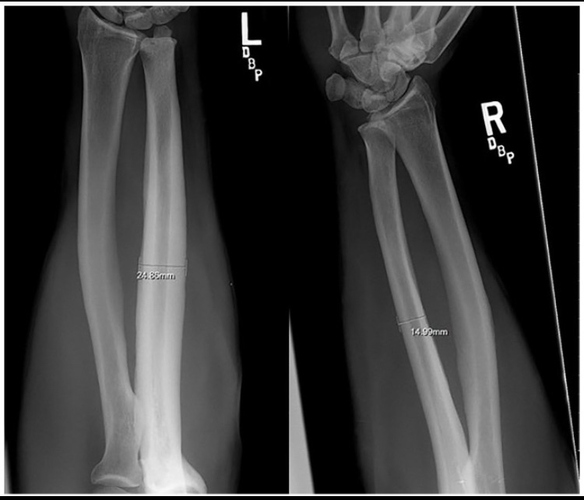

This study examined professional bareback rodeo riders (without a saddle), showing extreme bone hypertrophy in the ulna. The hypertrophy results from direct trauma and impact with the hip bone. For perspective, some individuals had up to a 92% increase in bone diameter and a 268% increase in cross-sectional area, which is extremely unusual. The image in the study shows significant hypertrophy, though not the individual with nearly doubled bone diameter.

If anyone claims this hypertrophy is caused by muscle pull alone, that is incorrect. The main reason is direct trauma to the bone, supported by the following:

- Many other sports generate high torsional forces on the bone, but hypertrophy does not exceed 10% compared to rodeo riders, indicating torsion alone cannot explain the extreme growth. Direct trauma plays a key role.

- The hypertrophy occurs only in the area where the humerus contacts the hip bone, exactly at the point of contact and impact. This localized growth confirms direct pressure and trauma are the main causes.

- Hypertrophy was observed only in riders without a saddle, where the humerus presses directly against the hip. Saddles act as a barrier that reduces direct pressure and trauma, preventing bone growth.

- The large variation in hypertrophy between individuals is due to some using protective pads that reduce trauma, while others did not. This shows how protection affects trauma and the extent of hypertrophy.

- Significant hypertrophy is seen in bareback riders, but not in saddle riders, further supporting that direct trauma and impact are the main drivers of bone growth.